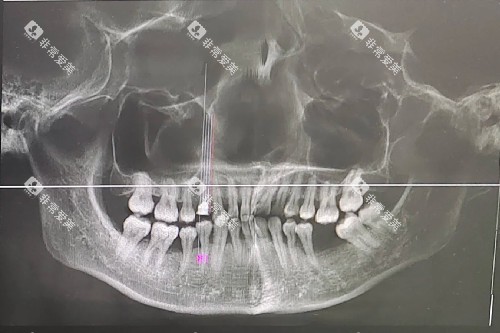

根管治疗是治疗牙髓炎、根尖周炎等牙髓疾病的有效方法。

它可以去除感染的牙髓组织,消除炎症,保存患牙。

美冠塔口腔根管治疗的收费通常根据牙齿的部位和根管数量来确定。

前牙的根管治疗相对简单,费用一般在 500 - 1000 元左右。

后牙由于根管数量较多,治疗难度较大,费用会相对较高,大约在 1000 - 2500 元。

如果根管情况复杂,需要进行多次治疗或使用特殊的治疗设备,费用可能会进一步增加。